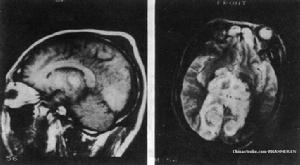

顱骨骨髓炎較易伴發硬腦膜外積膿,偶爾亦可因開放性顱骨骨折早期清創不徹底而引起,其時頭皮。傷口常已癒合。這類病人早期多有頭痛、發燒、嗜睡,當膿腫形成後往往出現顱內壓增高及局部腦組織受壓症狀,如偏癱、失語或神經廢損體徵。CT掃描檢查可見類似硬膜外血腫的梭形影像,早期呈低密度,一周以後漸變為等密度或高密度影。由於病灶區硬腦膜有炎性肉芽增生,能使內凸的硬腦膜顯著強化,呈緻密的弧形帶為其特徵。若為產氣菌感染,則可出現液平面及所氣體。硬腦膜外積膿的手術治療與顱骨骨髓炎病骨切除,硬腦膜外膿液及肉芽清除方法相似,已如上述。對靠近上矢狀竇或側竇的硬腦膜外積膿,應警惕血栓性靜脈竇炎的發生。一般在外科清除膿腫後,尚須繼續抗菌治療3-4周,同時,應適當給予抗凝治療,以預防靜脈竇血栓的發生。

(2)硬腦膜下積膿

硬腦膜下積膿預防保健